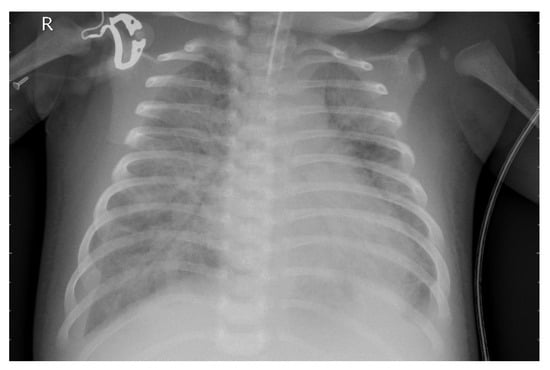

3.1. Dataset

3.2. Preprocessing